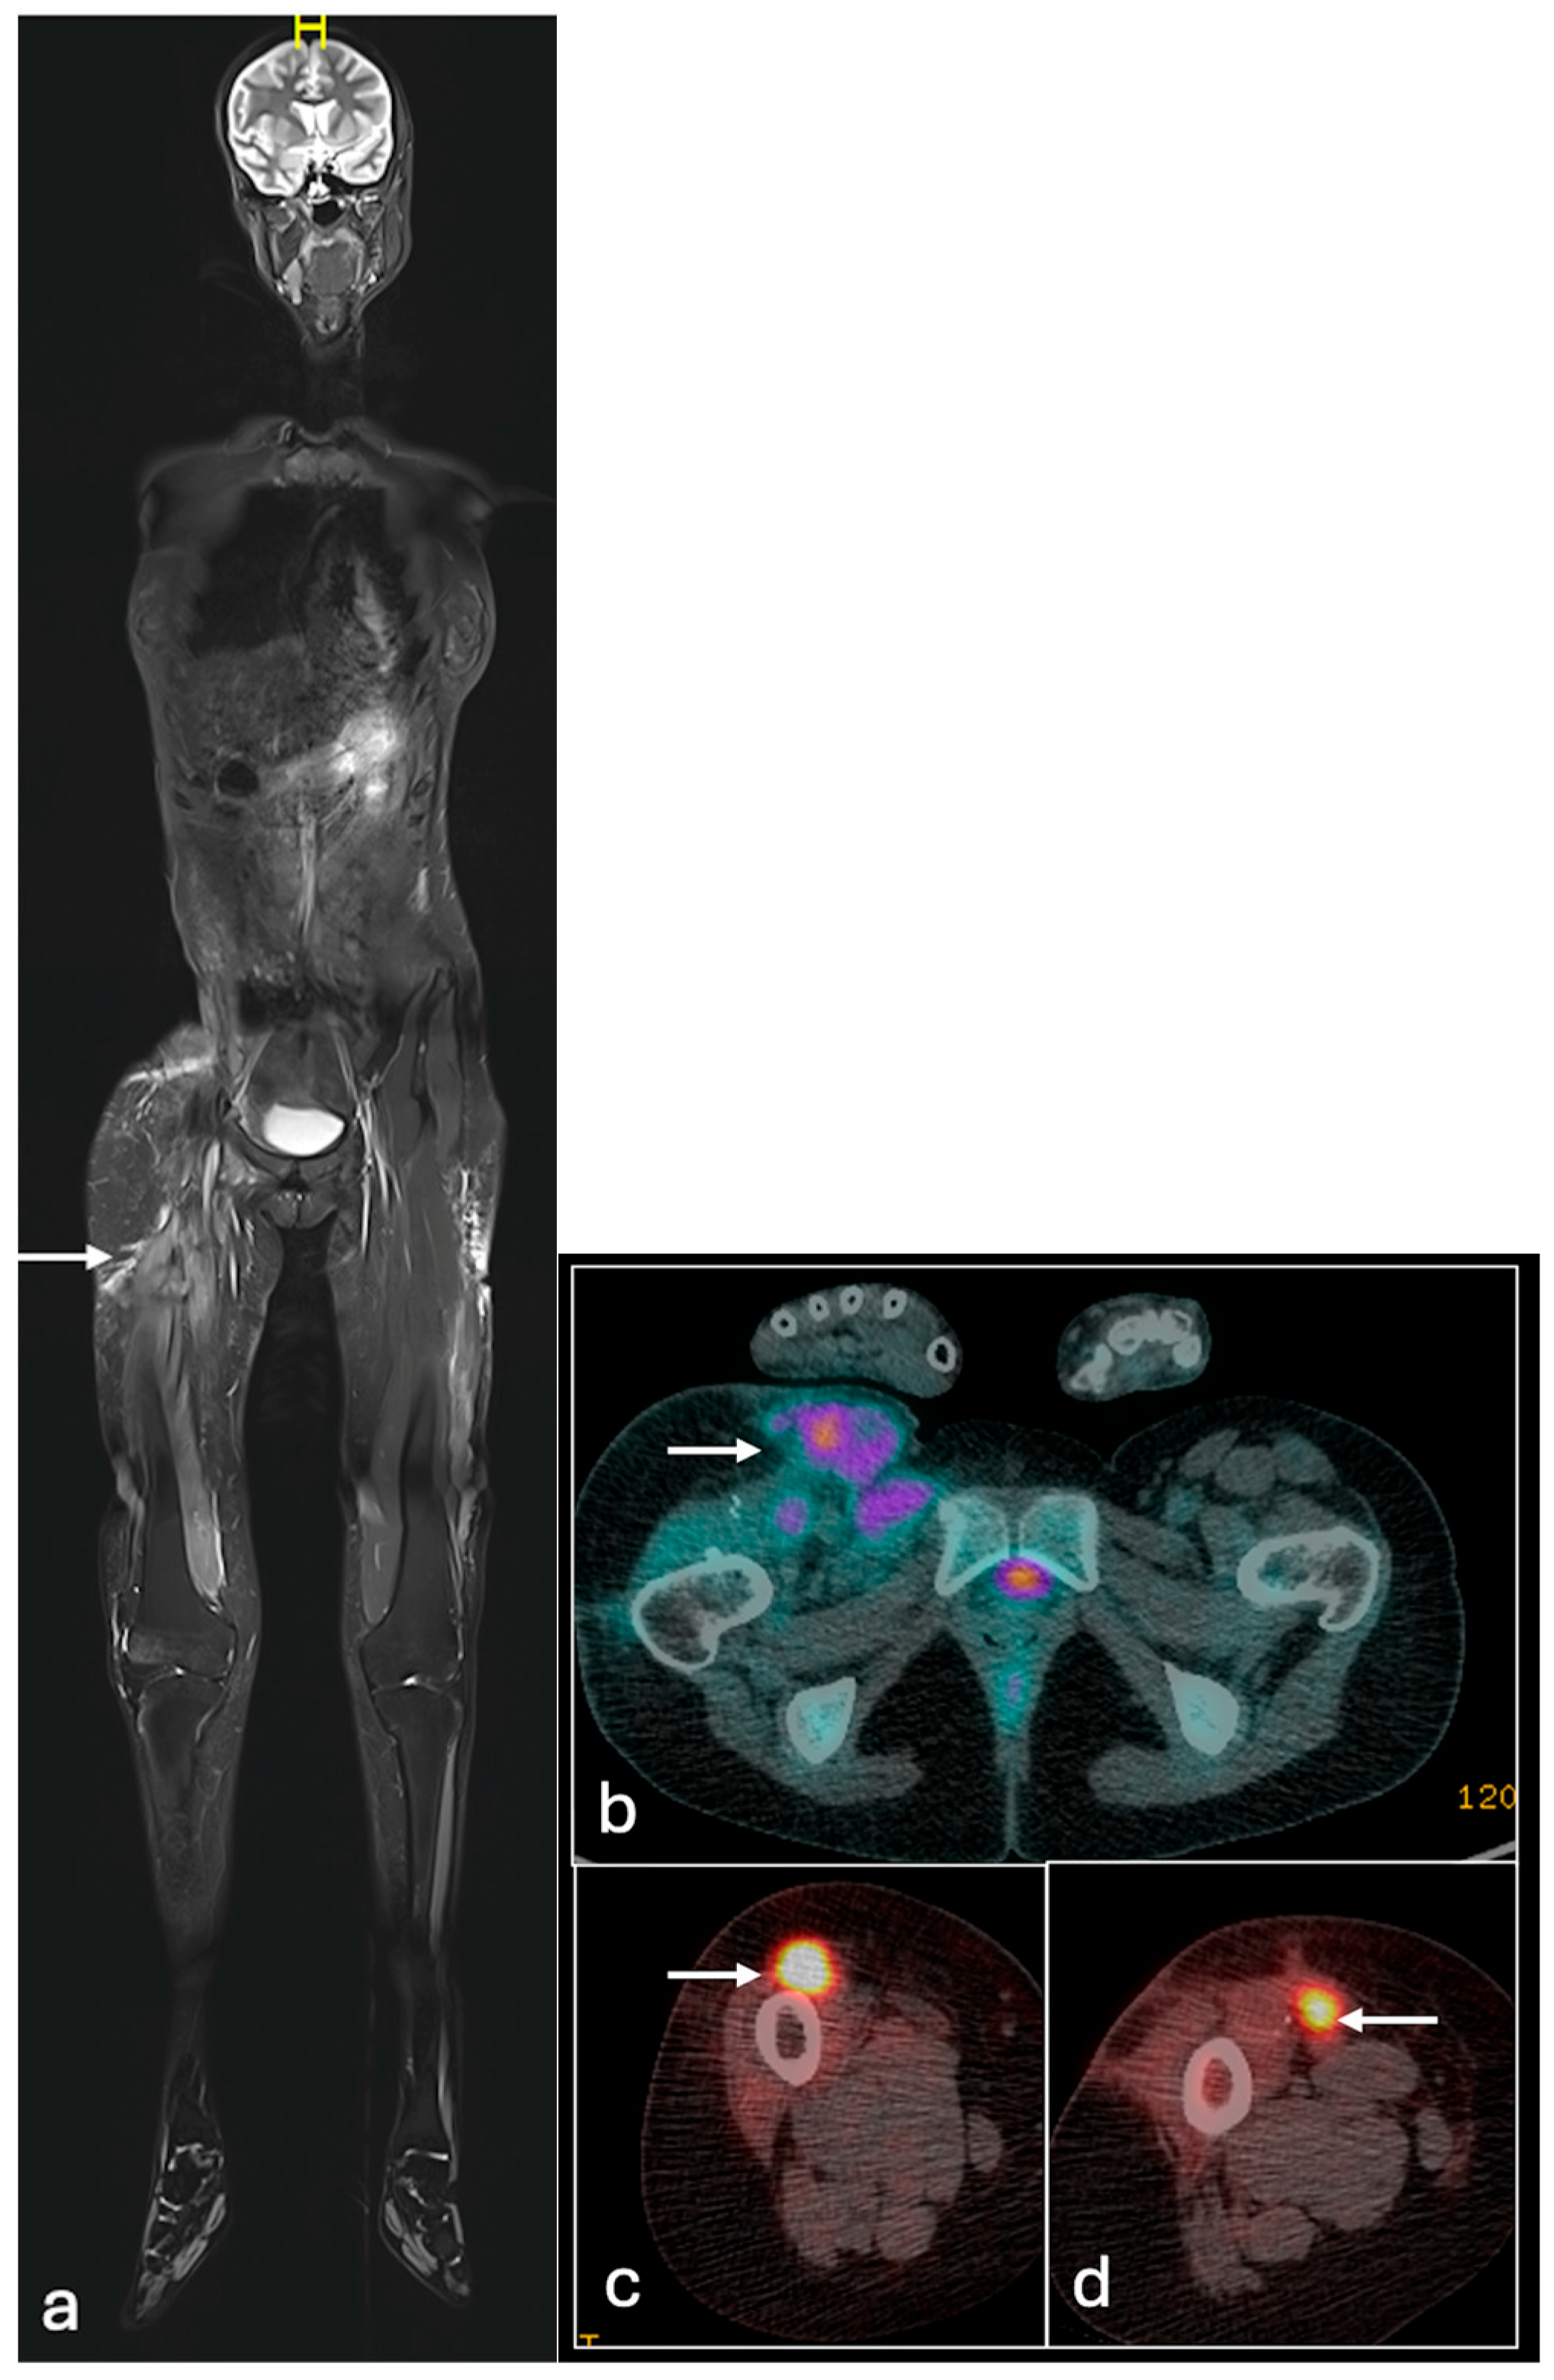

4.3. Ewing Sarcoma